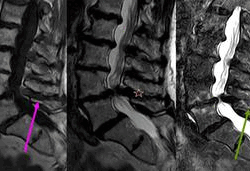

Por qué las hernias de disco se curan solas.

Tener dolor debido a una hernia discal es bastante habitual, se